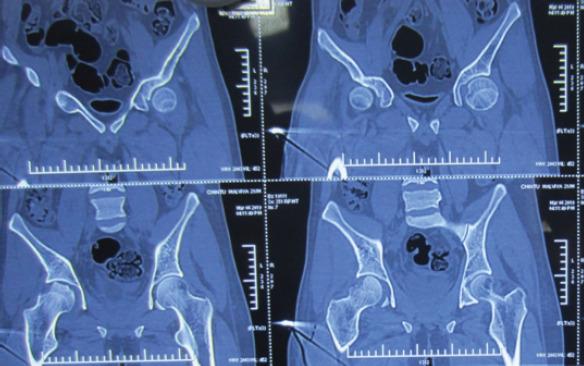

A 23-year-old male who sustained a high-energy trauma due to road traffic accident. He presented to ER with fracture of shaft femur, multi-ligament injury at the ipsilateral knee, fracture lower pole patella, ipsilateral fracture talus, and calcaneus along with comminuted fracture femoral head. He was managed by open reduction and internal fixation of the femoral head by safe surgical dislocation of the hip joint. Such injuries have been described rarely in the literature until now. The purpose of this report is to highlight the extreme rarity, possible mechanism involved, surgical management, and functional outcomes of such injuries.